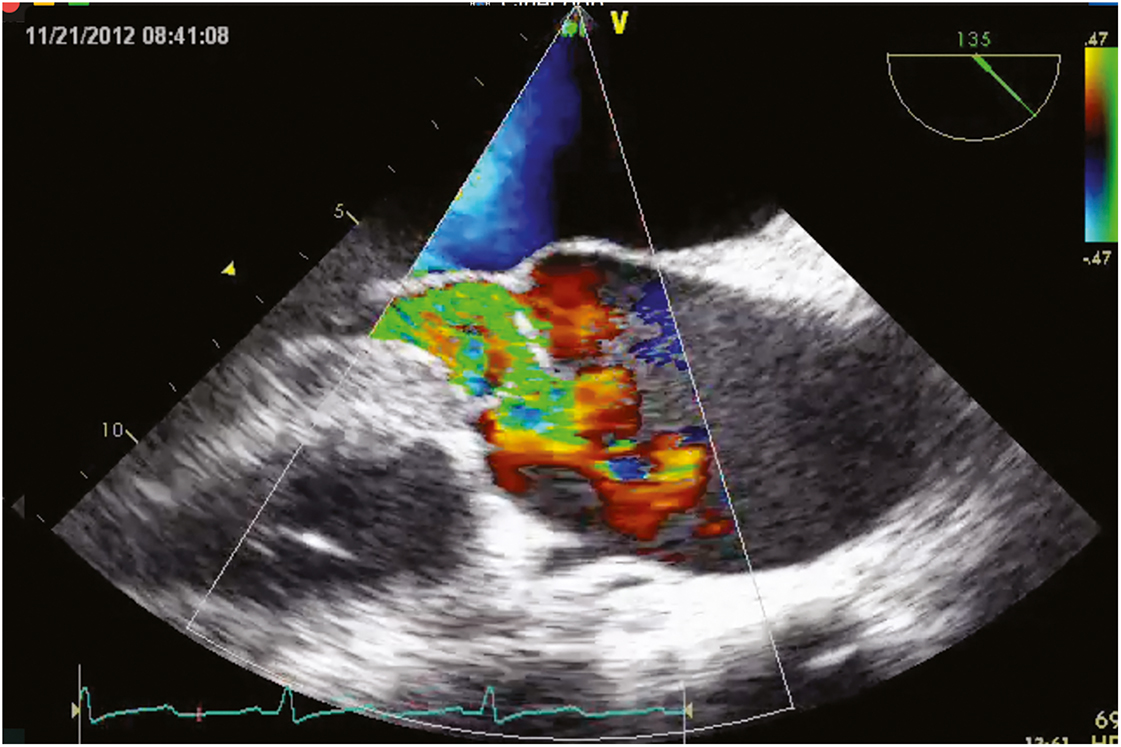

The severity of MS can be obtained by direct measurement of the diastolic gradient between the LA and ventricle at the time of cardiac catheterization. This requires a transatrial puncture, a procedure largely replaced by echocardiographic techniques. Echocardiographic diagnosis is based on gradient estimation by Doppler and by measuring the rate of decay in the pressure with the time spent in diastole (pressure halftime). The MV area (cm2) can be derived from an empirical formula wherein the MV area equals 220 divided by this pressure halftime. Severe MS is present when the mean diastolic gradient exceeds 10 mm Hg, corresponding to a valve area of less than 1.0 cm2 (Figure 7.18; Video 7.3).

In the presence of MR, ventriculography demonstrates reflux of dye from the LV into the LA. Severe MR is diagnosed according to the relative volume of regurgitant flow and flow reversal in the pulmonary veins. Color Doppler echocardiography permits similar quantification, as does spectral Doppler waveforms of pulmonary venous flow (Figure 7.19; Video 7.4).

Figure 7.19.: Transesophageal Echocardiographic Findings of Moderate Mitral Stenosis (Color Flow Doppler) with 3D View (Top) and 2d View (Bottom).

Transesophageal echocardiographic findings of moderate mitral stenosis (color flow Doppler) with 3D view (top) and 2D view (bottom).